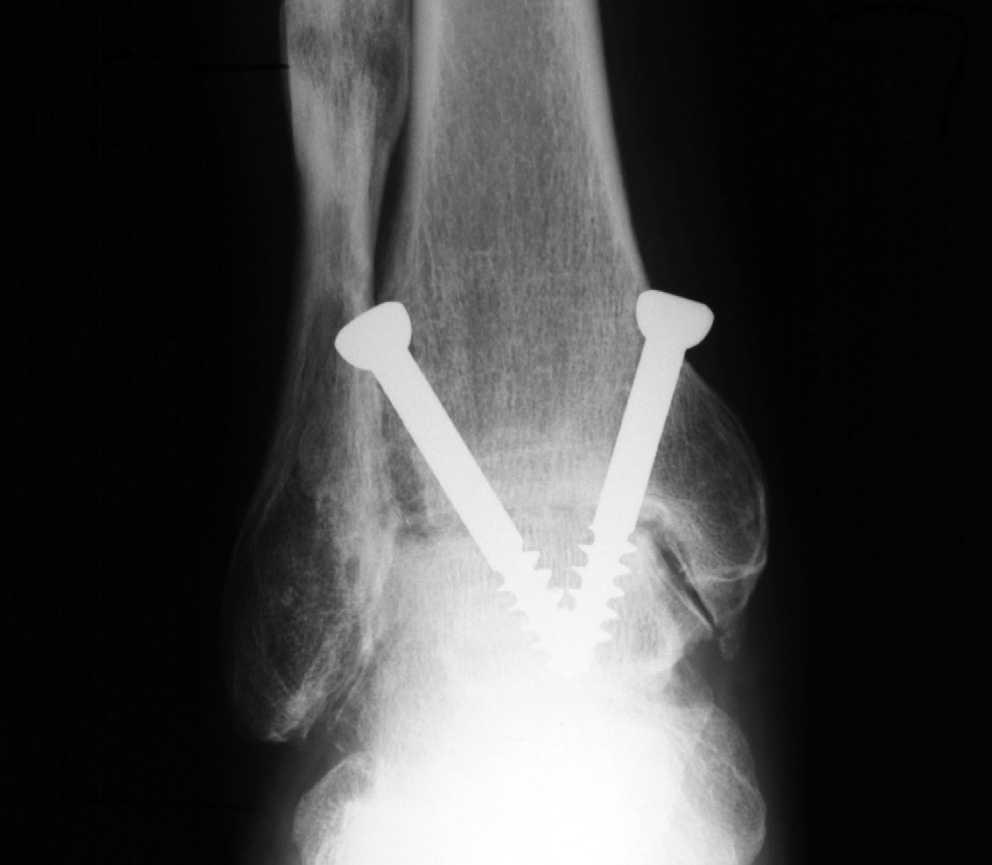

WebDiscapacidad por Artrosis de Tobillo o Rodilla La medición se centrará en la limitación de movimiento y en la anquilosis , en caso de existir. Todo ellos según las tablas 37 y 38 -si. WebLa incapacidad permanente por artrodesis es una realidad médico – legal cada vez más frecuente a la hora de reclamar la declaración de nuestro grado de incapacidad. WebLa artrodesis, por tanto, es un procedimiento, la mayoría de las veces quirúrgico, que persigue dejar sin movilidad definitivamente a una articulación. En el.

ARTRODESIS | Qué es, por qué se realiza, complicaciones, cuidados y tratamiento fisioterapéutico